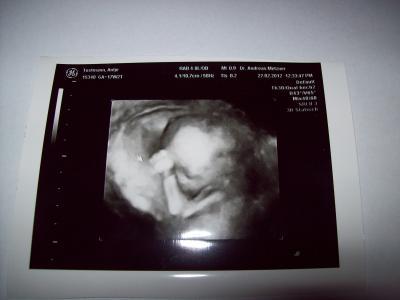

Hallo ihr lieben, wir waren heute auserplanmässig zum 3D US da mein FA diese möglichkeit nicht hat haben wir es bei einem anderen Arzt machen lassen hat 40 € gekostet und es war soooooooooooo toll, 45 Minuten konnten wir unserem Krümel zusehen beim turnen Strampeln und am daumen lutschen der Arzt war sehr nett und hat geduldig all unsere Fragen beantwortet und alles ganz toll erklärt. Und dann kam der große Moment Herzlichen Glückwunsch sie bekommen eine Tochter! Mein mann hatte gleich Tränen in den Augen das hatte er sich doch so gewünscht, der Doc hat zur Sicherheit noch 3 mal nachgesehen ne sagt er kein Zweifel ganz sicher das wird ein kleines Mädchen. Putz munter und gesund ist die kleine Maus durch meinen Bauch geturnt. Liebe Grüße

Bild zu Endlich Outing wir bekommen.................. - Forum für August - Mamis